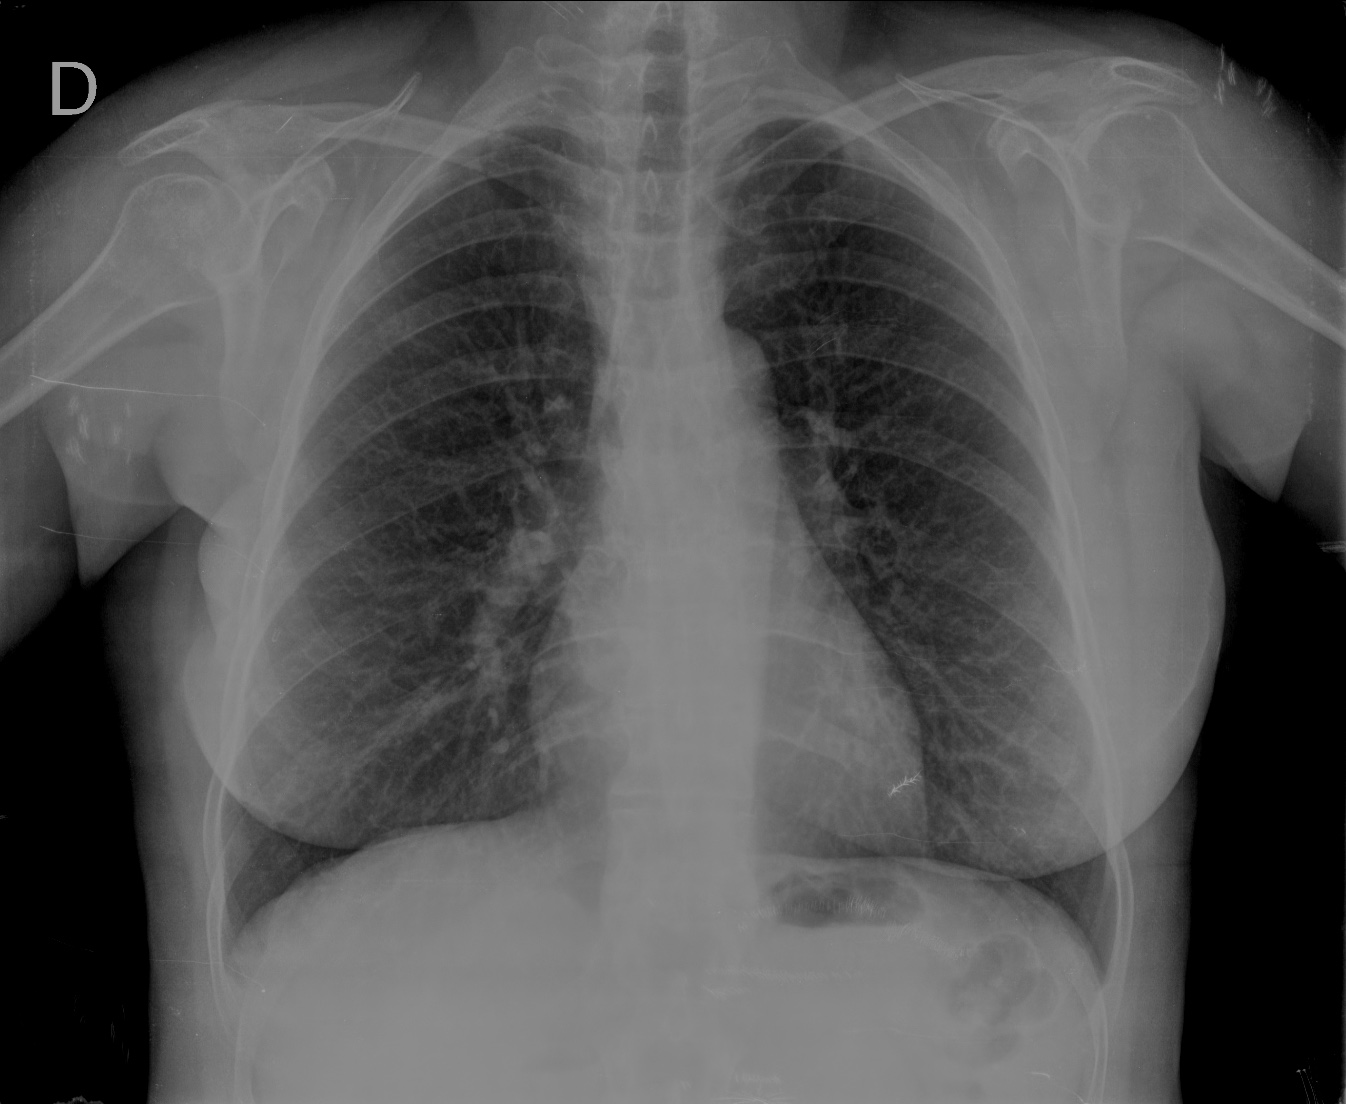

CASO: Revisión.

Hallazgos:

- Mastectomía derecha.

- Resto del estudio sin hallazgos de significación.

RECUERDA LA SISTEMÁTICA PARA NO OLVIDAR NINGUN HALLAZGO. A esta paciente le han extirpado la mama derecha, motivo por el cual se observa una asimetria entre las densidades de las bases pulmonares.